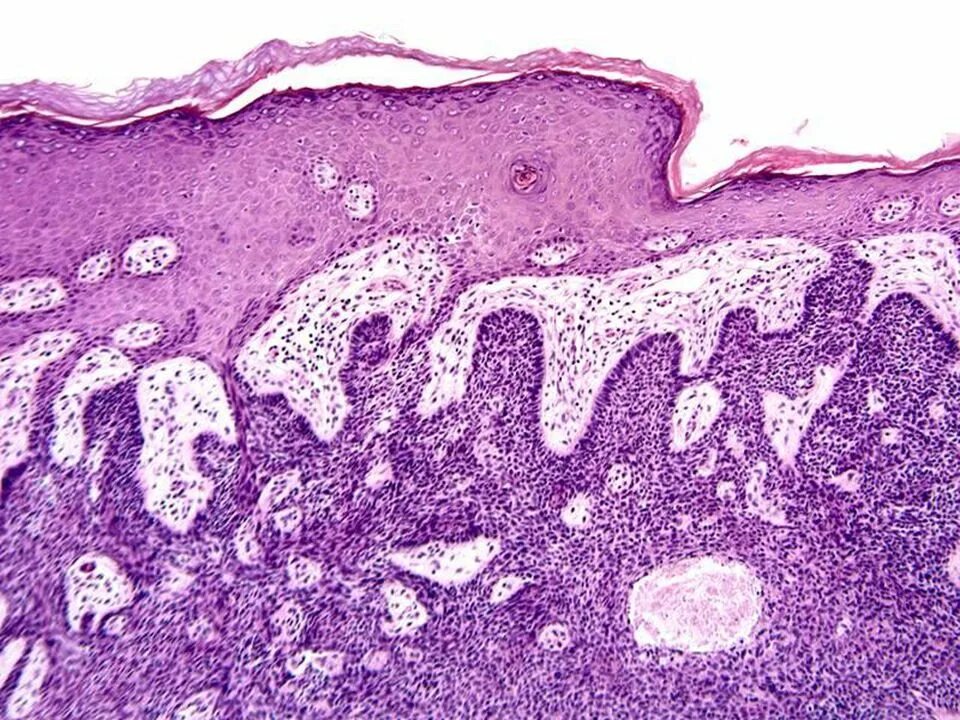

Гистология базалиома